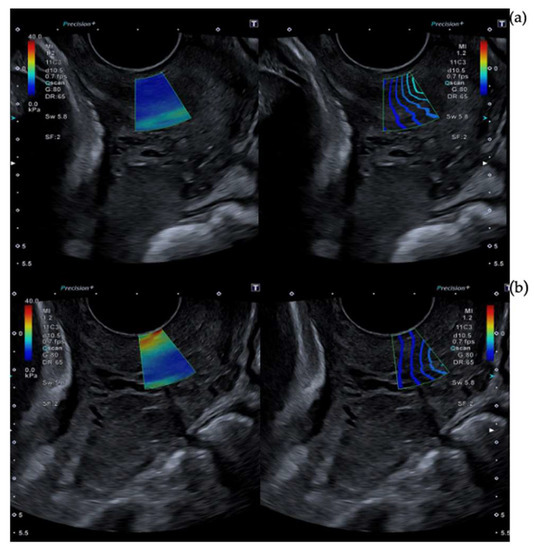

2.3. Cervical Shear Wave Elastography Measurement

- O’Hara, S.; Zelesco, M.; Sun, Z. Shear Wave Elastography on the Uterine Cervix: Technical Development for the Transvaginal Approach. J. Ultrasound Med. 2019, 38, 1049–1060. [Google Scholar] [CrossRef]

- Hernandez-Andrade, E.; Aurioles-Garibay, A.; Garcia, M.; Korzeniewski, S.J.; Schwartz, A.G.; Ahn, H.; Martinez-Varea, A.; Yeo, L.; Chaiworapongsa, T.; Hassan, S.S.; et al. Effect of depth on shear-wave elastography estimated in the internal and external cervical os during pregnancy. J. Perinat. Med. 2014, 42, 549–557. [Google Scholar] [CrossRef]

| Anterior cervical lip | 8.40 (7.15–10.30) | 7.75 (6.25–9.40) | 7.45 (5.95–8.85) | p < 0.01 | p 0.06 |

| Posterior cervical lip | 9.60 (7.40–11.85) | 8.65 (7.0–11.20) | 8.40 (6.65–10.10) | p 0.06 | p 0.01 |